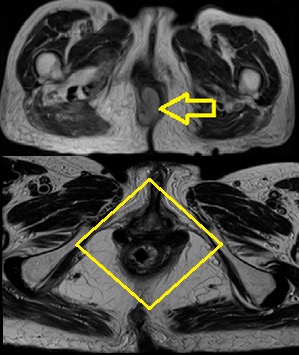

La resonancia nuclear magnética (RNM) detectó en canal anal, hemi-circunferencia derecha (hora 9) lesión sólida polipoide con pedículo de 6 x 10 mm, de límites bien definidos y delimitados (Figura 3).

Figura 3: RNM de pelvis con corte transversal. Figura 3a: lesión sólida de canal anal, que ocupa hemicircunferencia derecha, de aspecto polipoide, con pedículo de 6 x 10 mm. Límites bien definidos. Figura 3b: RNM post tratamiento, donde evidencia remisión de la lesión sólida de canal anal.

En la evolución se realizó control con RNM a 3 meses de finalizado el tratamiento radioterápico, presentando remisión de la lesión sólida de canal anal (Figura 3). Manteniendo respuesta clínica completa a 6 meses de la última RNM.

En el caso presentado se realizó TC de abdomen-pelvis, RMN de pelvis y PET-scan, donde se evidenció además de la lesión de canal anal, una adenopatía ilíaca derecha configurando así un estadío III.